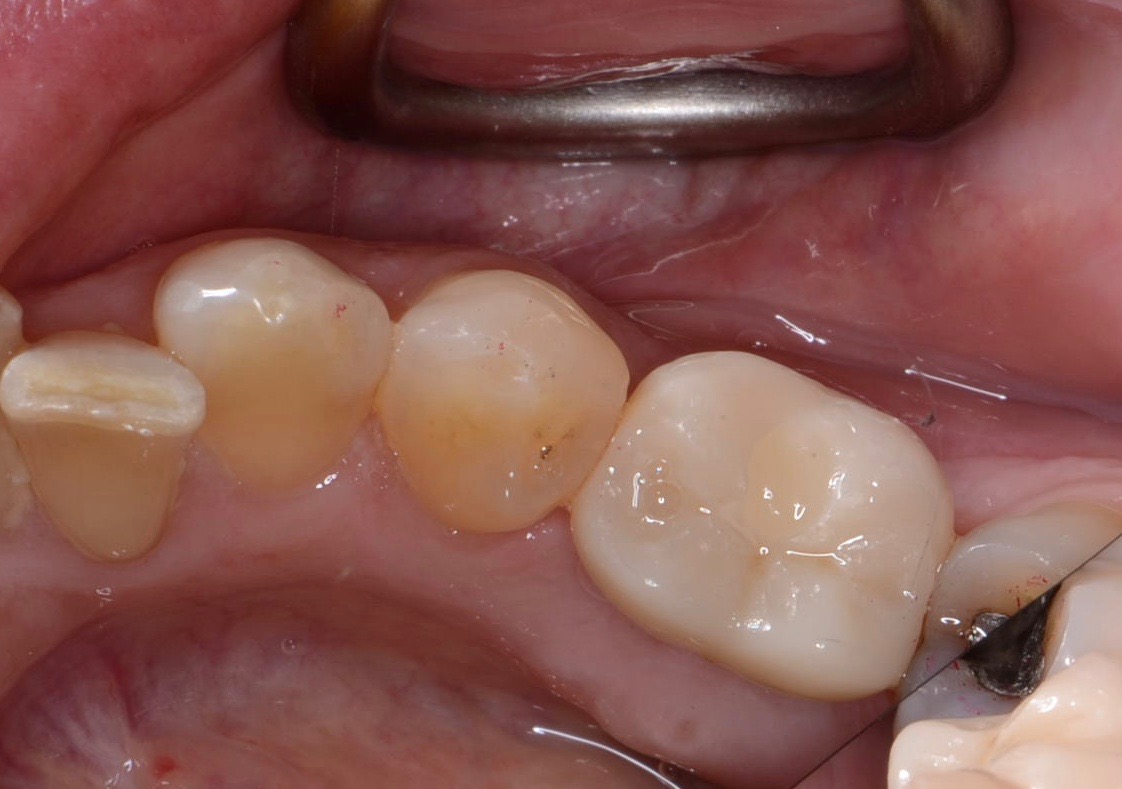

Fig 12. Path of draw necessitates adjustment to adjacent tooth or cement-retained restoration.

Figure 12